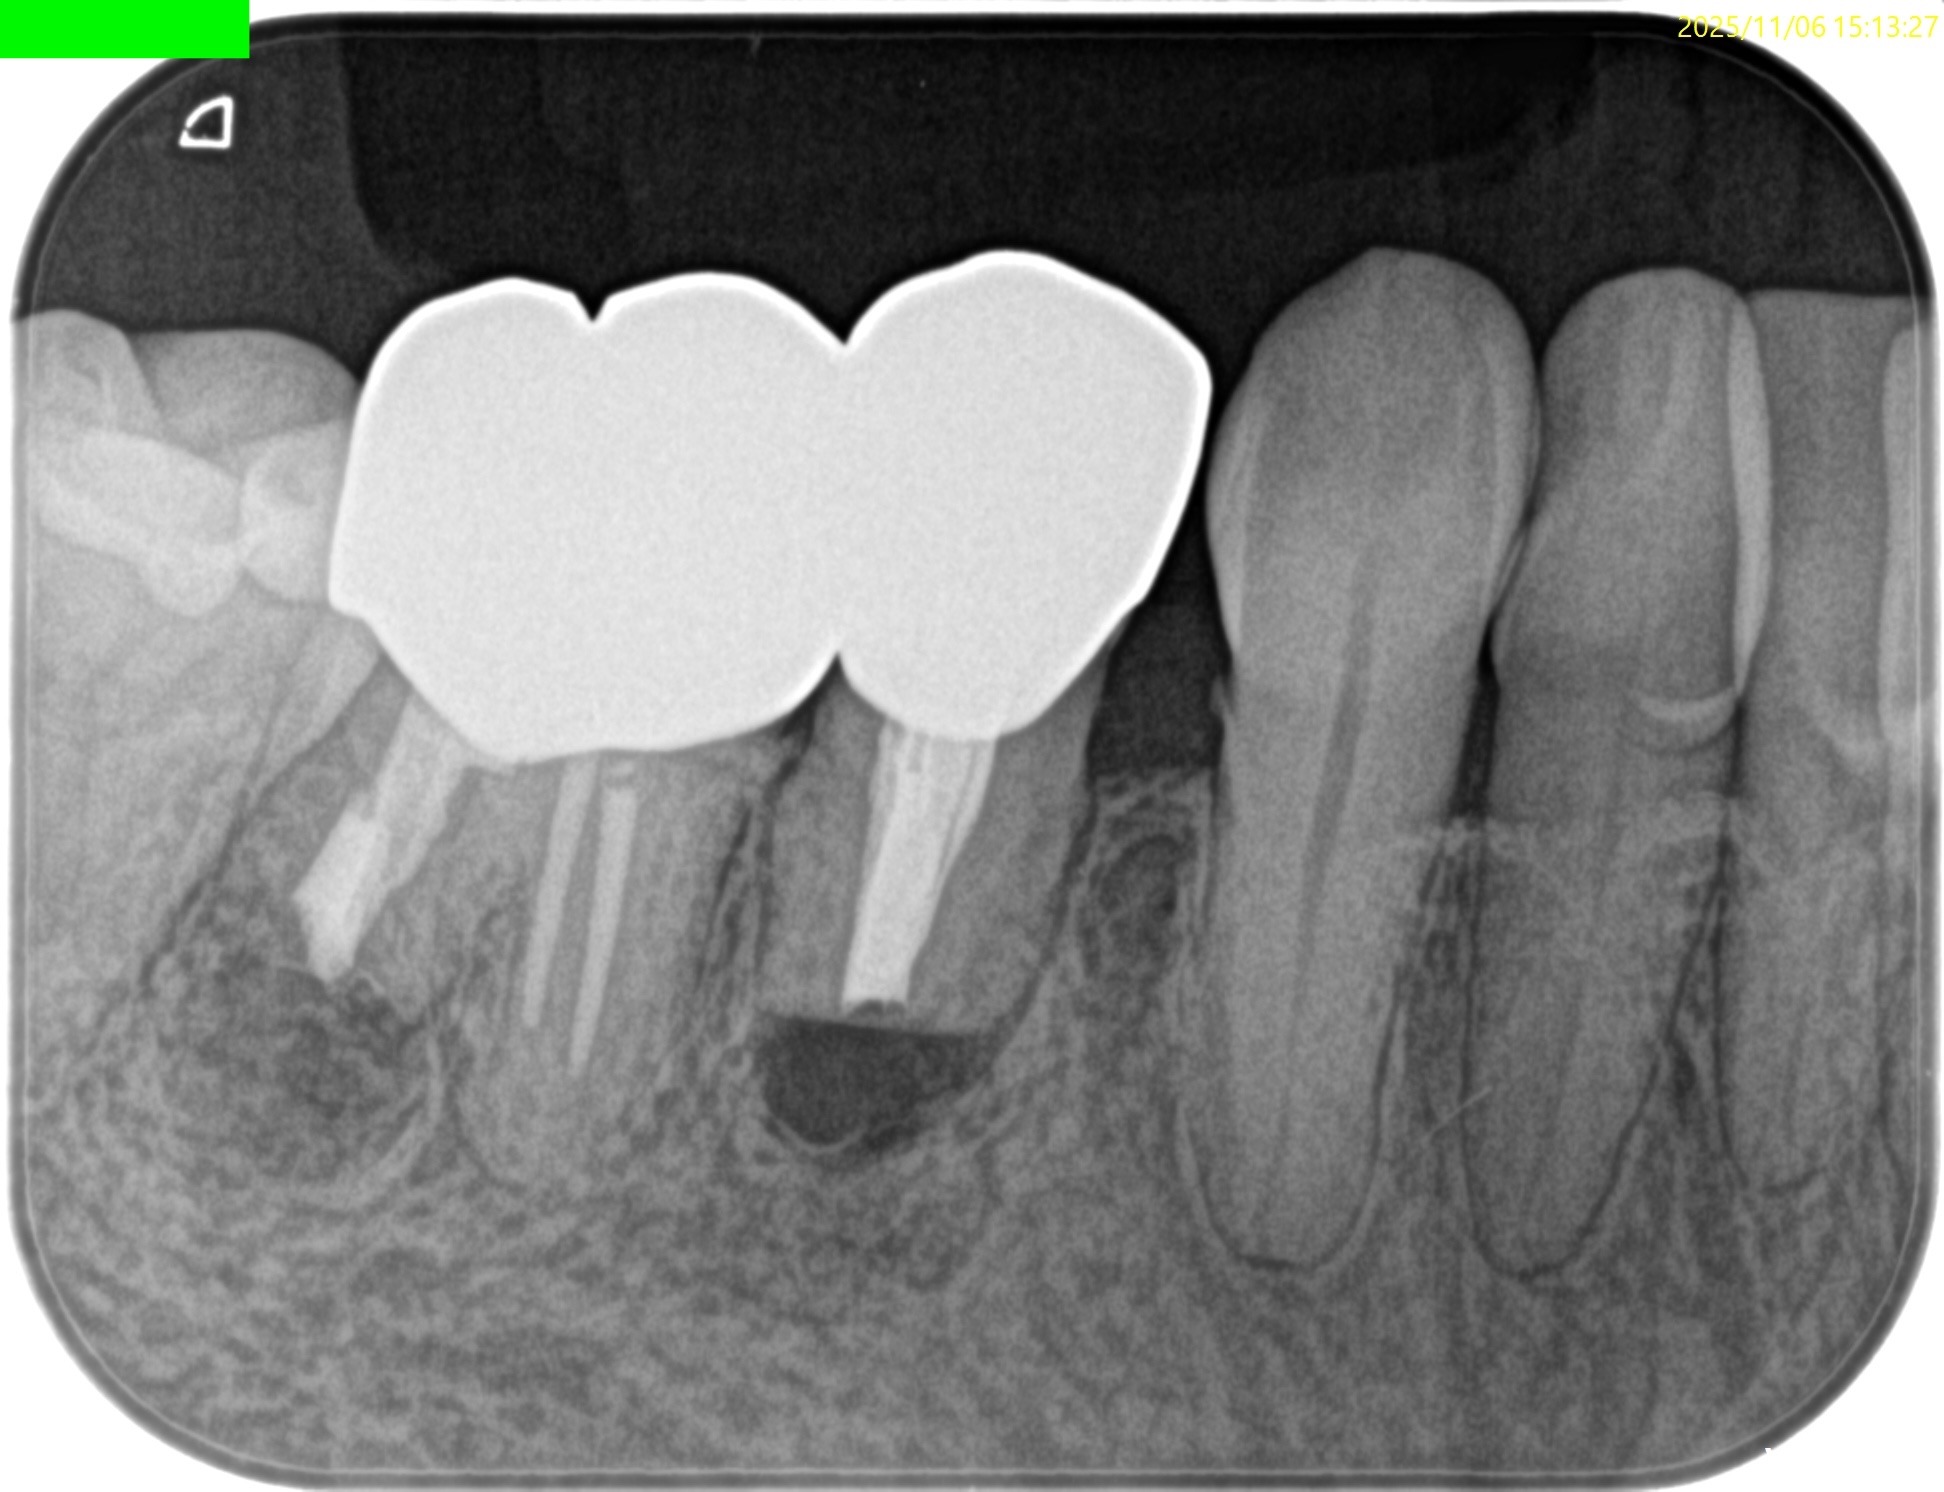

PAを撮影した。

PA, CBCTを撮影した。